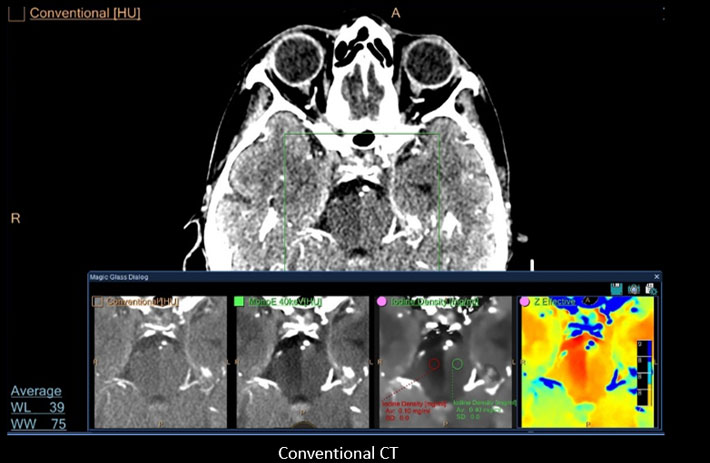

Mit dem Spektral-Detektor-CT werden Spektraldaten automatisch bei jedem Scan erfasst. Die Informationen stehen jederzeit auf der Scankonsole, der CT-Workstation sowie an jedem PACS-Arbeitsplatz zur Verfügung, sodass es nicht notwendig ist, den Patienten erneut zu scannen, bspw. wenn initial zufällige Anomalien festgestellt wurden. Dadurch profitieren Anwender durch eine höhere Diagnosesicherheit und weniger Nachuntersuchungen auf anderen bildgebenden Systemen. Unsere Fallsammlung zeigt, welchen klinischen Mehrwert der Spektral-Detektor-CT in unterschiedlichsten Anwendungsbereichen in der klinischen Routine bringt. Jede Woche gehen neue Fälle live.